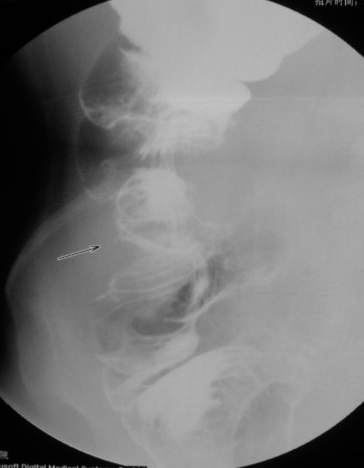

67岁女性,腹痛、腹胀半月余。查:右侧腹部有触痛,可触及肿物。

支持升结肠肿瘤性病变。

常规考虑---结肠癌,不排除诱发肠套叠了。

支持升结肠癌。

支持考虑升结肠癌。

谢谢大家讨论。与x6045完全不同。本例手术结果为右侧结肠旁沟及盆腔多发脓肿。术后病人恢复良好,现已出院。

感谢楼主反馈结果!造影见果核征,首先考虑肿瘤,即使误诊也应该这样考虑。